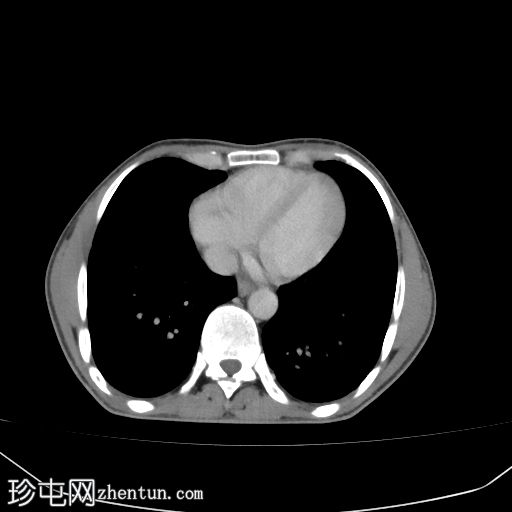

腹部(肝脏)CT

轴位

平扫

肝硬化征象包括表面和实质结节、实质异质性、右后肝切迹征和容积重分布。

门静脉可见肿瘤血栓,表现为血栓强化。

肝脏可见无数细小病灶,动脉期呈非环状强化,门静脉期呈消退,提示弥漫性肝细胞癌。

其他发现包括腹水和左侧肾上腺可疑增厚。